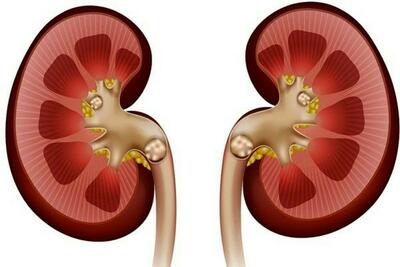

نارسایی کلیه

رابطه مصرف مسکن در بیماران میگرنی و آسیب به کلیه

یک جراح کلیه و پروستات با اشاره به پیشگیری و درمان بیماریهای کلیوی توضیحاتی ارائه کرد.

عدم کنترل قند خون موجب نارسایی کلیه

فوق تخصص کلیه دانشگاه علوم پزشکی بابل عدم کنترل قند خون را موجب نارسایی کلیه دانست.

راه های محافظت از سلامت کلیه ها

رکنا: سلامت کلیه ها بسیار مهم است.

اهمیت تستهای سالانه عملکرد کلیوی از ۴۰ سالگی به بعد

نارسایی مزمن کلیه یک بیماری خاموش است که فرد مبتلا ممکن است سالها از آن بیاطلاع باشد؛ علل ایجاد کننده این بیماری، اغلب به بیماریهای دیابت و فشار خون بالا بازمیگردد.